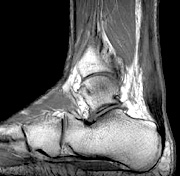

- Copyright – Stock Photo / Register Mark Sagittal T1 Most chiropractors treat patients who have musculoskeletal problems. This patient population is often being treated concurrently with medications for the same complaints. To complicate matters even more, some of these patients may even be seeking chiropractic care for symptoms that are caused by medications, of which neither the patient nor their chiropractor is aware.

The following is a case history:  A 55-year-old long-distance runner who is a regular chiropractic patient has a main complaint of right SI joint pain that is intermittent and aggravated by long periods of standing, walking or running. He had this problem before and generally only needs a couple of adjustments to relieve his symptoms. He also had some minor, bilateral calf pain with minimal tenderness in both Achilles tendons, which he stated was not uncommon when he was training to run in a marathon. Unfortunately, he failed to mention that three weeks previously, he had suffered a urinary tract infection and was given a 10-day course of Cipro. He was examined and given a chiropractic adjustment, with a recommendation to return in two days for another adjustment. He was also told to take it easy in terms of running for the next few days until his symptoms abated. He continued to run, with increasing symptoms mainly involving his right calf, with tenderness and swelling in the right Achilles tendon. He returned to his chiropractor, who immediately sent him for an MRI of his right Achilles tendon. The MRI demonstrated a partial tear of the tendon.